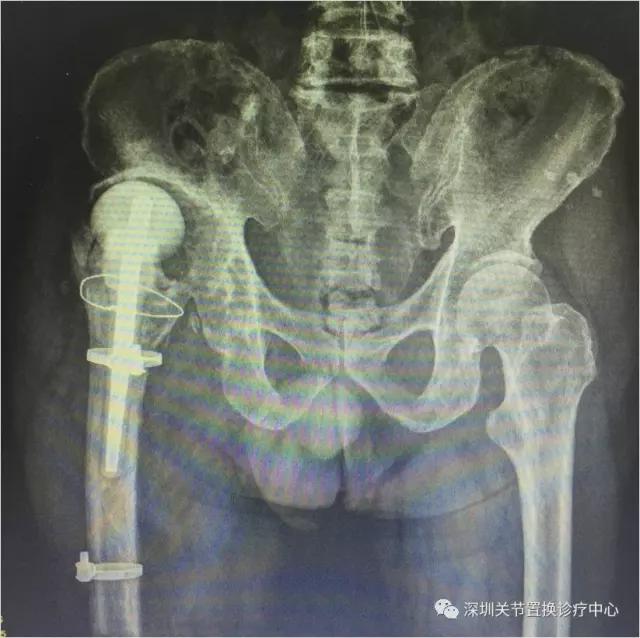

第二次术后X线片

老人家又可以行走啦!!